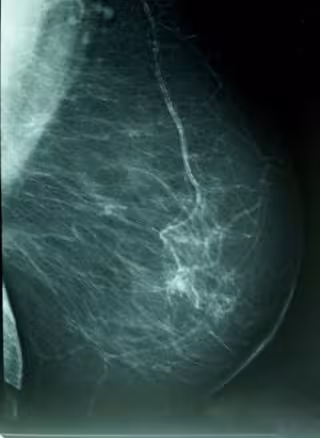

Cáncer De Mama, Densidad Mamográfica

En cuanto al cáncer de mama, aunque la mayoría son esporádicos, entre un 5 y un 10 por ciento se deben a mutaciones en línea germinal de genes específicos de susceptibilidad al cáncer con una penetrancia elevada.